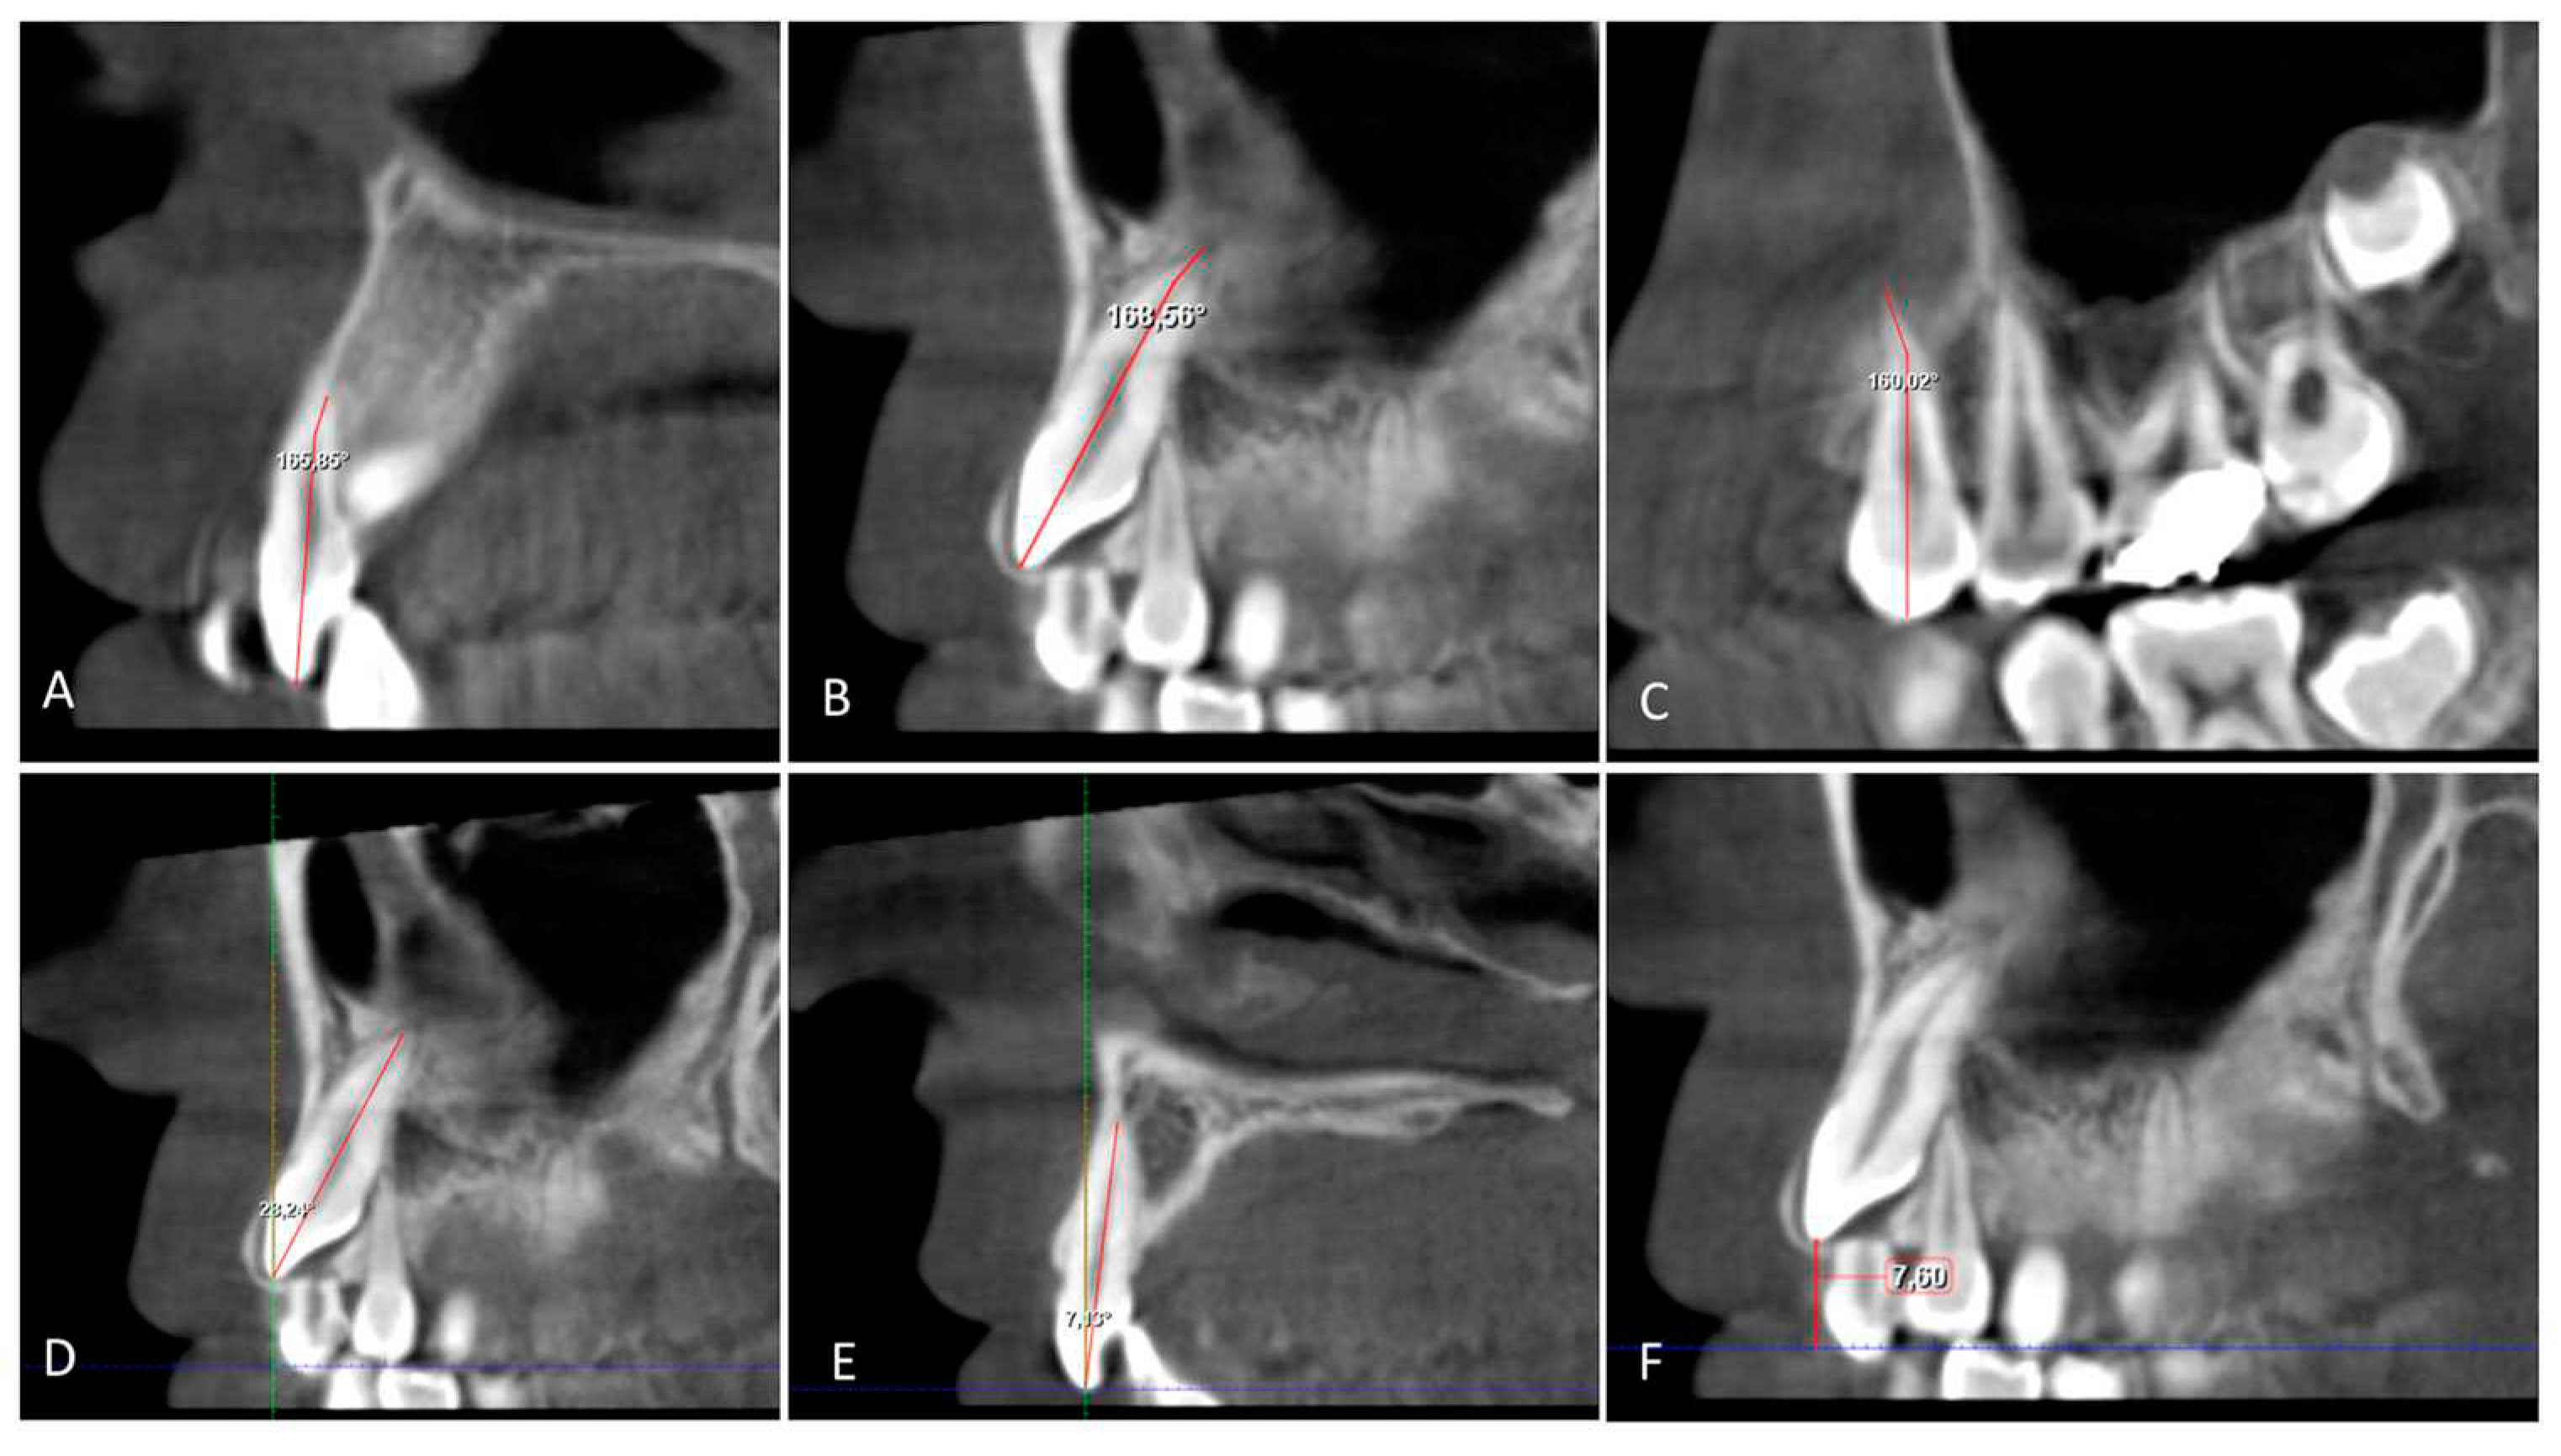

The angulation of the maxillary impacted canine (U3Ang), the lateral incisor (U2Ang), and the first premolar (U4Ang) to the vertical line is determined from the sagittal section by the resulting angle between a line parallel to the midline and a line on the long axis of the lateral incisor, the canine, and the first premolar. The angle between the long axes of the impacted canine and the adjacent lateral incisor (U3/U2) (Figure 3).

Figure 6. A. B. C. The angle root dilaceration of canine (U3 RD), lateral incisor (U2 RD) and 1.premolar (U4 RD); the angle between a line to long axis of tooth and a line of the root apex on the sagittal section. D. E. Inclination of canine (U3 Inc) and lateral incisor (U2 Inc); the angle between a line 90° to the occlusal plane and a line to the long axis of the canine and lateral incisor on the sagittal section. F. Vertikal Distance to occlusal plane from canine crown (U3 VD); distance from cusp tip of canine crown to the occlusal plane on the sagittal section.

The inclination of the maxillary impacted canine (U3Inc) and lateral incisor (U2Inc) is determined from the sagittal section by the resulting angle between a line parallel to the midline and a line to the long axis of the lateral incisor and canine (Figure 6). The angle of dilaceration of the root (RD) between the long axis of the tooth and the apex of the root of the impacted canine, the lateral incisor, and the first premolar in the sagittal section (Figure 6).